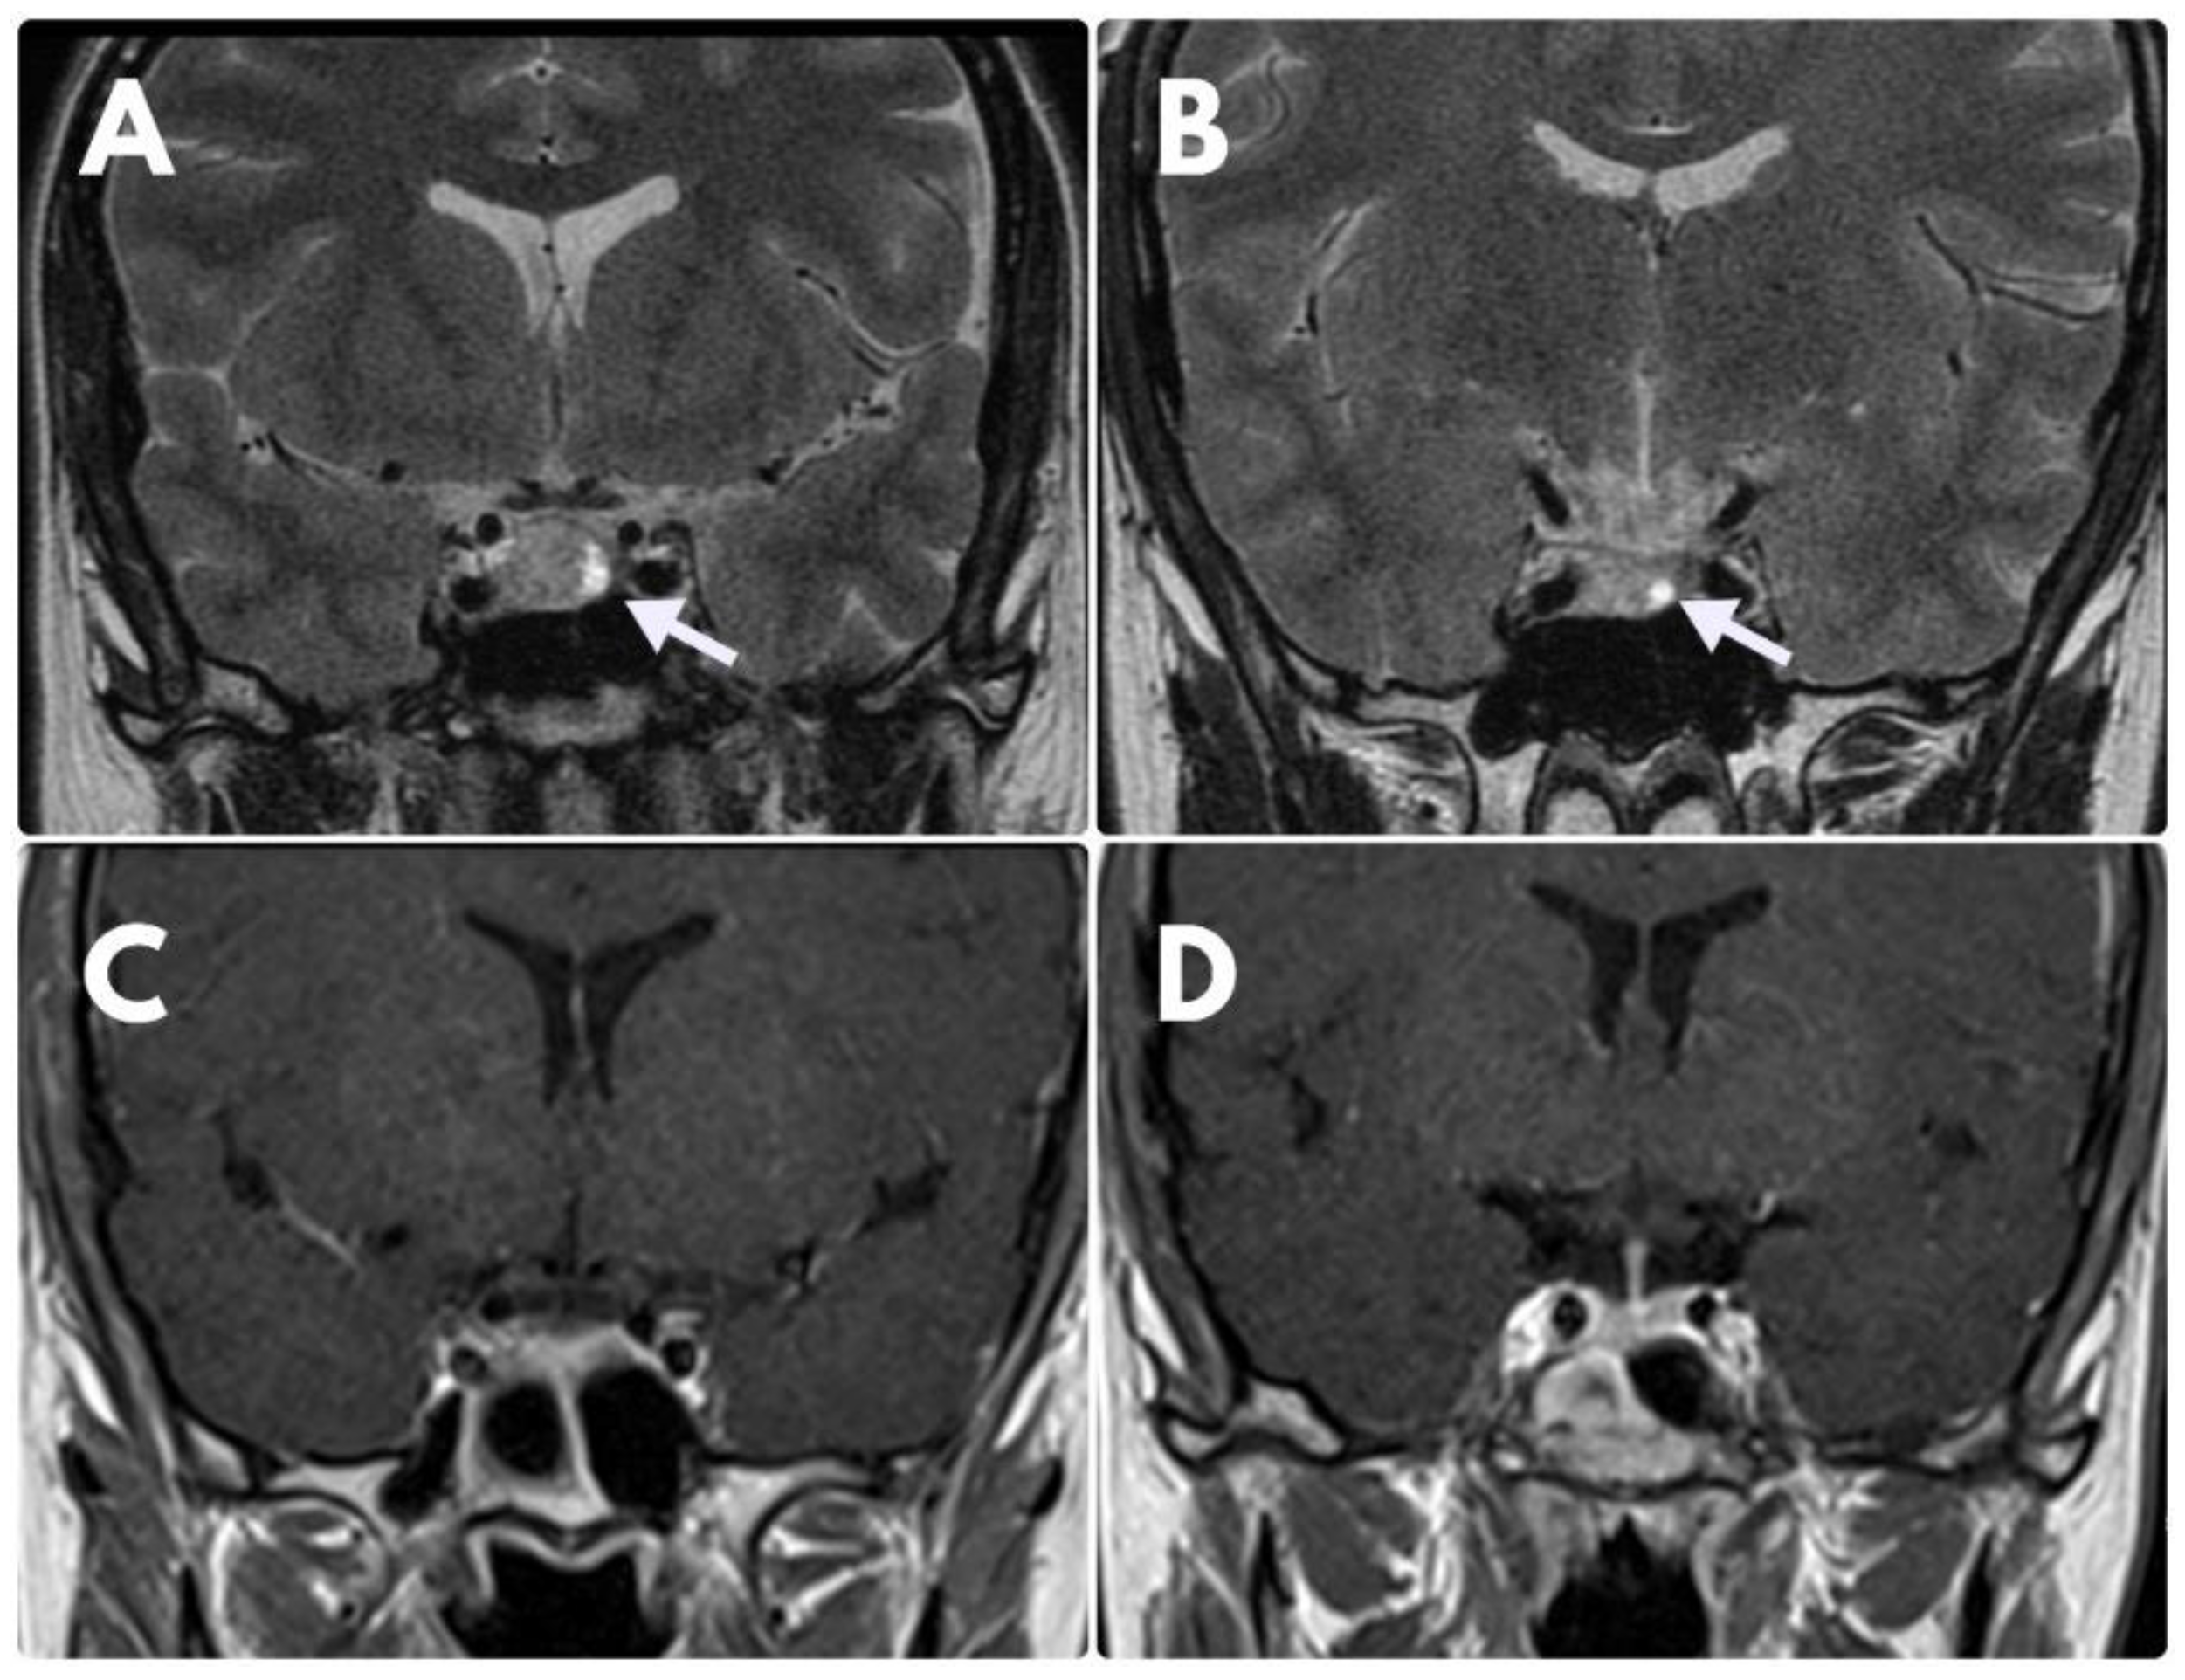

On account of lack of clinical and biochemical improvement, no regression of the tumour on MRI scans as well as DAs-resistance, the patient underwent transsphenoidal resection of the tumour in March 2019. Histological analysis revealed a sparsely granulated lactotroph adenoma with positive immunostaining for PRL and Ki-67 index >3%. In the postoperative period, CAB at the dose of 3.5 mg/week was reinstituted due to persistent hyperprolactinemia. A control MRI (February 2021) showed the complete disappearance of the initial pituitary lesion (Figure 2).

Figure 2. MRI coronal images. (A)—MRI at the time of diagnosis—visible suspicious hyperintense area at the left side of the pituitary gland (white arrow), which was diagnosed as an adenoma. (B)—control examination after 6 months of BRC treatment disclosed no significant regression of the lesion. (C,D)—control MRI after operative treatment—no visible signs of adenoma.